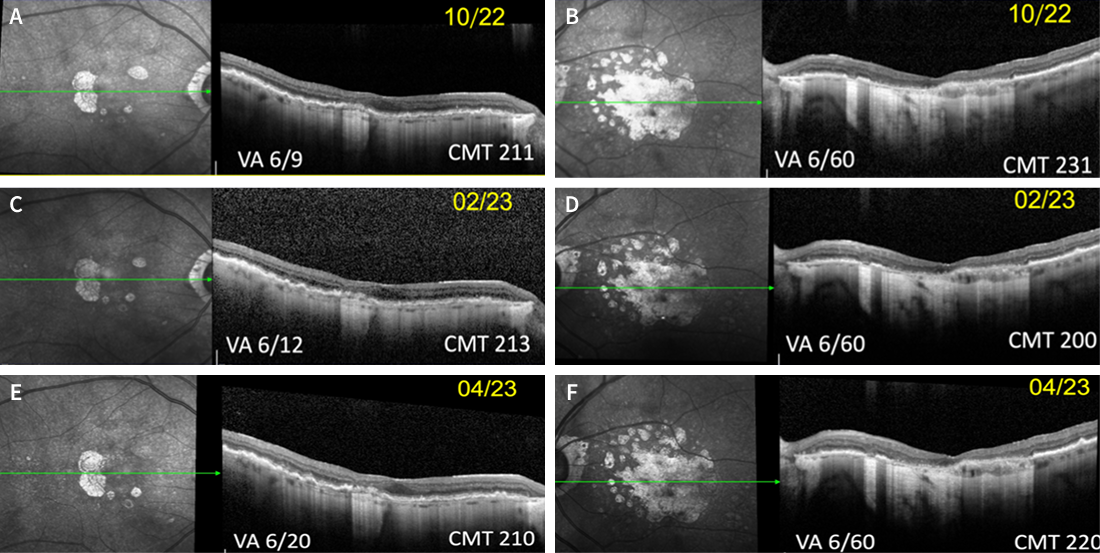

The patient was then followed in our clinic for routine monitoring of each eye in November 2023, January 2024, and March 2024 (Figure 5). As shown in Figure 5F, the patient developed sub-foveal bleeding in the left eye in March 2024. No treatment was offered for the left eye at that time, and the patient was directed to return in 1 month for continued monitoring. During this visit, in April 2024, the sub-foveal bleeding in the left eye demonstrated signs of resolution; however, for the right eye, the decision was made to restart anti-VEGF treatment. The patient was subsequently administered intravitreal aflibercept injections in April, May, and June 2024. OCT follow-up in the right eye is shown in Figure 6, and in the left eye in Figure 7.

<p>Figure 5. OCT images from routine monitoring visits of the patient over time. Figures A (right eye) and B (left eye) are from November 2023; figures C (right eye) and D (left eye) are from January 2024; and figures E (right eye) and F (left eye) are from March 2024.  </p>

Figure 5. OCT images from routine monitoring visits of the patient over time. Figures A (right eye) and B (left eye) are from November 2023; figures C (right eye) and D (left eye) are from January 2024; and figures E (right eye) and F (left eye) are from March 2024.